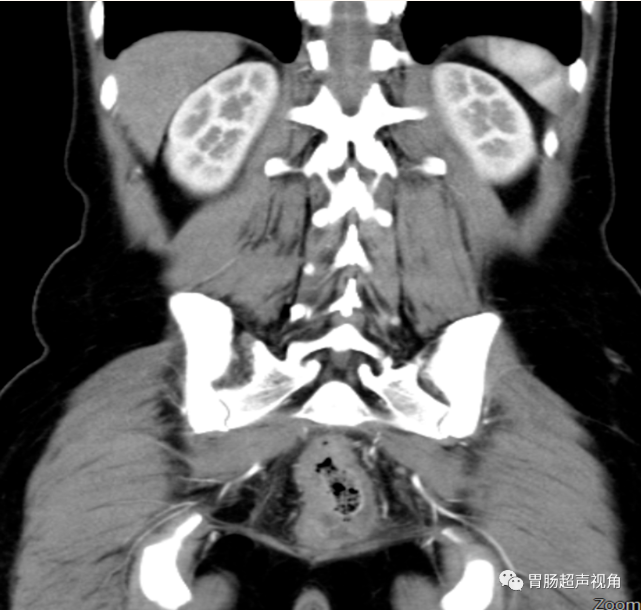

• CT示:

子宫颈后缘见团片状低密度影,增强扫描呈弱强化,直肠后壁及右侧壁局灶性增厚。